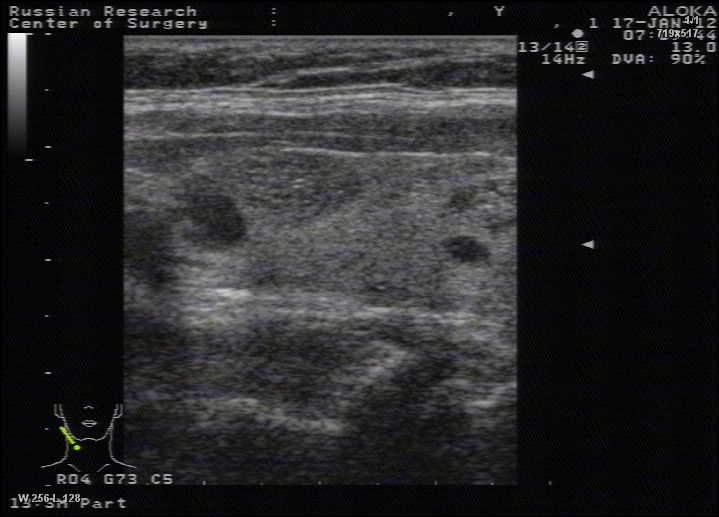

TI-RADS 4. Узлы более 1,0 см в диаметре с “малыми” признаками злокачественности для выполнения ПУНКЦИИ (рис. 3):

- солидные узлы, равномерно или неравномерно умеренно пониженной эхогенности;

- солидные узлы изо- или гиперэхогенные, имеющие “малые” признаки злокачественности:

– гипоэхогенные включения;

– округлая/шаровидная форма;

– неравномерно утолщенное хало;

– макрокальцинаты.

Рис. 3. TI-RADS 4: а – узел шаровидной формы, с ровными и четкими контурами, умеренно пониженной эхогенности, с участками более низкого эхо, с макрокальцинатом. Узел окружен тонким хало (фолликулярная неоплазия); б, в, г (поперечное и продольное сканирование левой доли ЩЖ) – изоэхогенные узлы с гипоэхогенными включениями, с четкими контурами, с тонким хало (фолликулярная аденома); д – изоэхогенный узел с гипоэхогенными включениями, с неравномерно утолщенным хало (фолликулярный рак).